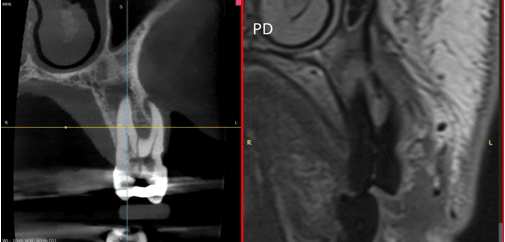

MRI has evolved into a powerful imaging technology in most medical fields. Interestingly, in dentistry the technique has so far been mostly limited to imaging of the soft tissues within the temporomandibular joint (TMJ). However, soft tissues play a major role in many diseases in dentistry and maxillofacial imaging, yet imaging has until now largely relied solely on radiographic techniques. Consequently, MRI offers a potentially powerful imaging solution with many applications in dental imaging. In parallel with this existing imaging gap, recent technological advances, particularly in lowfield MRI, have significantly reduced operational challenges. In 2024, following a two-year period of dentistry-specific beta development at Aarhus University, a 0.55 T MRI system tailored specifically to the imaging needs of dentistry was brought to market. This seminar summarizes the background of MRI applications in dentomaxillofacial imaging and presents clinical images from several applications acquired with this dedicated low-field scanner.